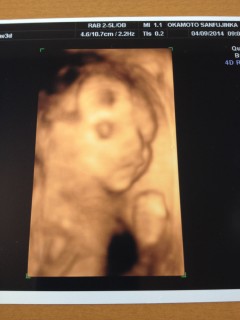

はじめての4Dエコーに感動でした!顔の前で手をモゾモゾ動かしていてとても可愛かったです。まだお肉がなくて顎がシュッとしてるな~ 25週0日相当の大きさでした。

初めての3D.4Dエコーしました! まだ週数が若いからやせ細って見えるとのことでしたが、顔つきや手足を確認できて夫と喜びました。 奇跡的にこちらを向いて手を振ってくれてるポーズをしてくれるサービス精神旺盛の我が子に笑顔がこぼれました!